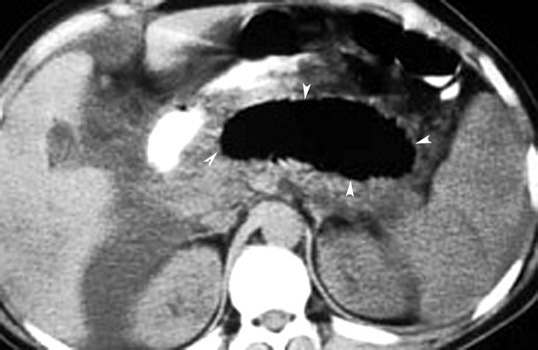

Pancreatitis with lesser sac abscess